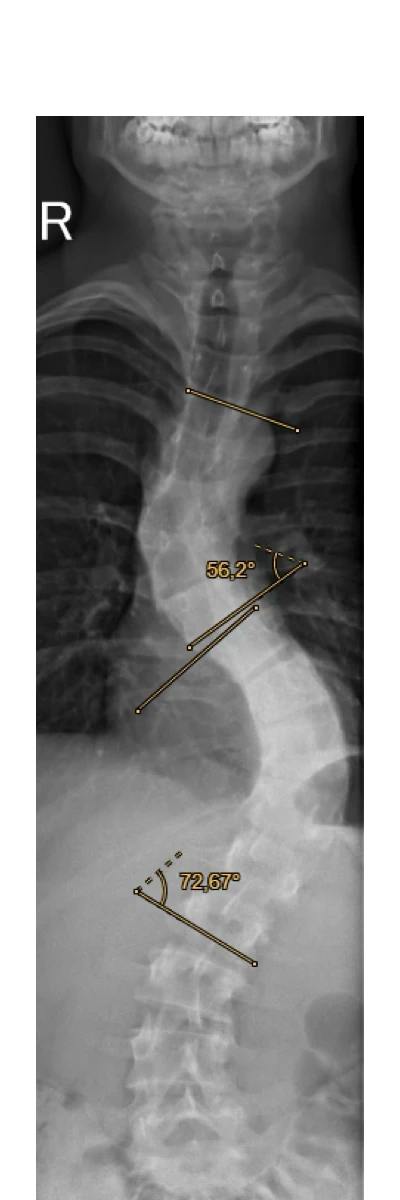

Im April fand die Röntgenuntersuchung statt. Als wir das Röntgenbild erhielten waren wir schon sehr geschockt. Die Wirbelsäule wies zwei Verkrümmungen auf und sah für uns sehr heftig aus.

Nachdem sich Herr Dr. Desai ein umfassendes Bild gemacht hatte, mich noch einmal eingehend untersuchte und sich die Röntgenbilder angesehen hat, sprach er uns seine Behandlungsempfehlung aus. Er erklärte uns alles sehr ausführlich und empfahl uns die klassische Wirbelsäulenversteifung bei einer Skoliose. Es sollten zwei Abschnitte in der Wirbelsäule die einmal 74 Grad und einmal 58 Grad Cobb Winkel aufwiesen soweit möglich begradigt werden. Herr Dr. Desai sprach von einer schweren und langen Operation, die 6 bis 7 Stunden dauern könne. Er wies auf die möglichen Komplikationen der Operation hin und erklärte uns auch ausführlich die möglichen Konsequenzen, wenn wir uns gegen die Operation entschieden.

In den Monaten bis zur Operation hat sich die Skoliose noch einmal deutlich verschlechtert.

Pre-OP Röntgenbild

mit Cobb-Winkel